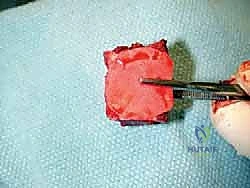

الخطوة الرابعة: تنظيف العظم والترقيع (Debridement and Bone Grafting)

يتم تنظيف الأنسجة الملتهبة والأكياس العظمية. ونظراً لأن مفصل (Agility) يترك فراغاً كبيراً بعد إزالته، يتم استخدام طعوم عظمية (Autograft من حوض المريض أو Allograft من بنك العظام) لملء الفراغات وبناء أساس قوي.